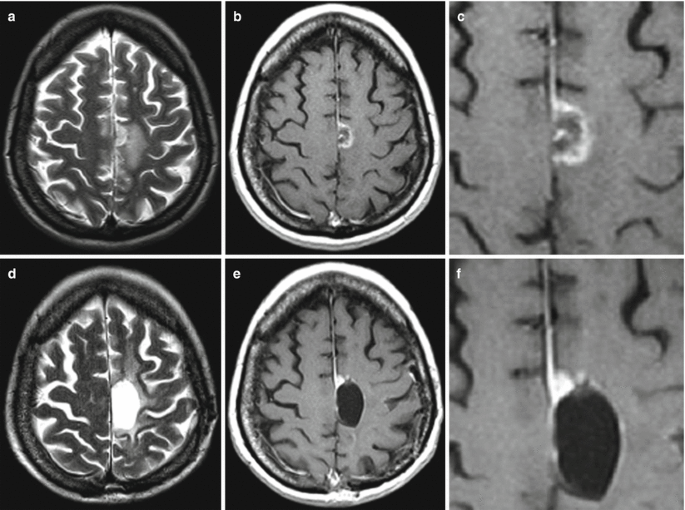

An Mri Based Deep Learning Approach For Efficient Classification Of Brain Tumors Springerlink